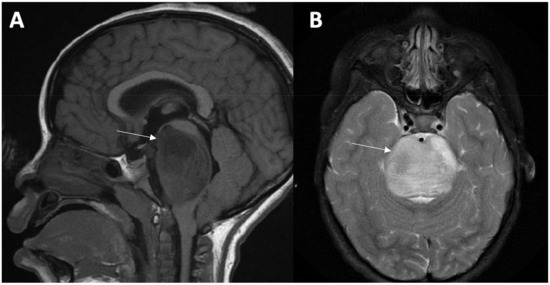

5. Imaging